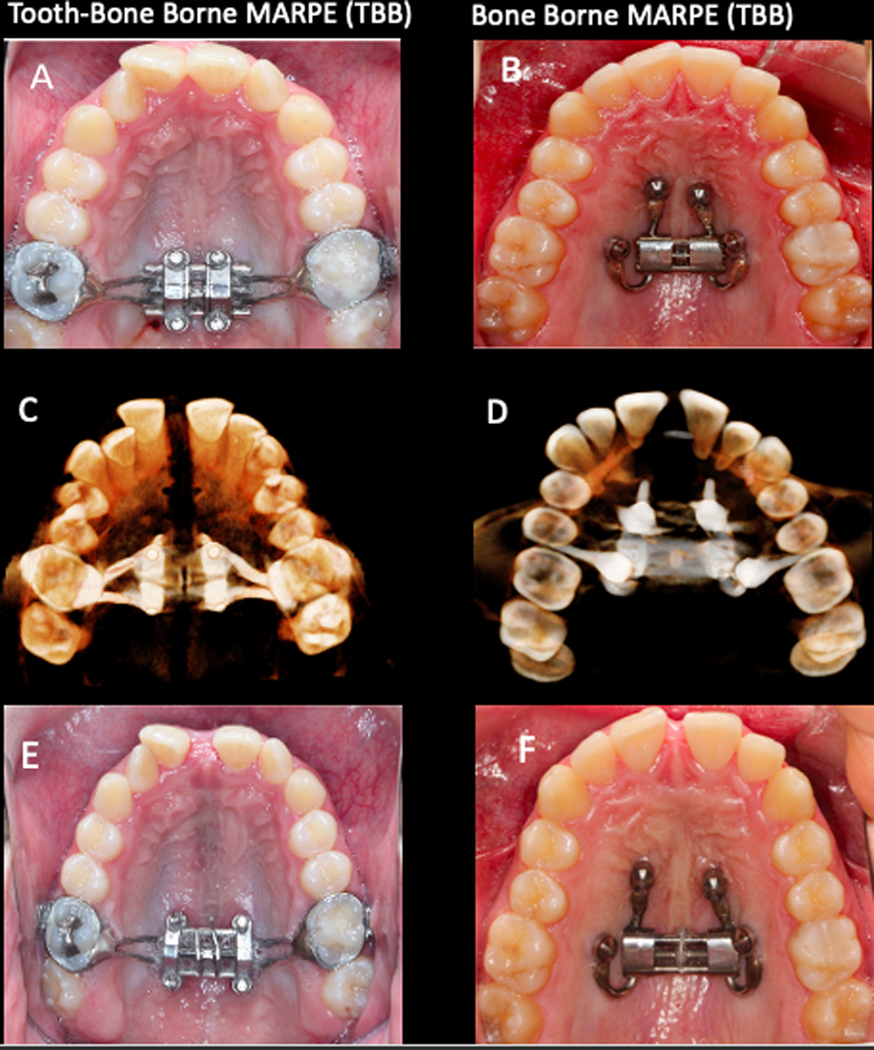

This investigation was a retrospective study of consecutively treated patients. This study was approved by the Institute of Review Board HUM00205476 The sample included a total of 30 individuals, 17 females and 13 males. Records of two groups according to the two types of appliances used were evaluated: CBCT scans of Group TBB (tooth-bone borne; Fig. 1A) was collected from clinical database archives at he University of West Virginia. and Group BB (bone-borne; Fig. 1B) was treated with bone supported anchorage in a private practice. Both groups include 15 patients. Ethnicity distribution is described in table I. The mean age was 18.8 ± 4.7 years (minimum age: 13 years; maximus age: 29 years) and 18.4 ± 5.9 years (minimum age: 8.8 years; maximus: 28.8 years) for Group BB and Group TBB, respectively.

Figure 1.

A and B, Maxillary occlusal view depicting the designs of the expanders before the activation (T1): A, TBB; B, BB. C and D, 3D rendering of the CBCT scan with appliance in place at T2 in an inferior view: C, TBB; D, BB. E and F, Maxillary occlusal view showing the end of the expansion with the appliances still in place: E, TBB; F, BB.

Types of expanders.

The tooth-bone borne (TBB) expander consisted of a central expansion jackscrew with four attached arms soldered to orthodontic bands placed on the maxillary first molars (Fig. 1 A). The addition of four sheaths welded to the body of the central expansion jackscrew allowed for the placement of the miniscrews in the palate. The miniscrews were 1.8 mm in diameter and varied from 8 to 12 mm in length, depending on what was required to achieve bicortical engagement. The palatal mini screws were placed symmetrically and parallel to the midpalatal suture. The miniscrews also were positioned posteriorly without extending into the palatine process (maintaining bony anchorage in the hard palate maximizes orthopedic forces to the pterygoid plates). The jackscrew was placed as close as possible to soft tissues, without impingement to avoid entrapment of food particles.

The bone- borne (BB) expander design used in the other group of patients included 4 miniscrews. Two miniscrews were placed in the anterior area of the palate, at the level of the third rugae. The two other miniscrews were inserted between the second premolar and the first molar (where the root distance is more favorable), at 6–8 mm from the alveolar crest (Fig. 1 B). If anatomic conditions prevented placement of the miniscrew such an ideal position, an alternative site was selected at the level of the second premolar between the nasal and sinus cortical bone, with the miniscrew having a more vertical inclination. Miniscrews used in Group BB varied between 9 and 15 mm in length, while the diameter was 2 mm for all patients (Spider Screw; Hdc, Thiene, Italy). For each patient, 2 insertion guides were designed and 3-dimensionally printed, including 2 sleeves each in cross position: one guide included an anterior-left and posterior-right sleeves and the other an anterior-right and posterior-left sleeve.